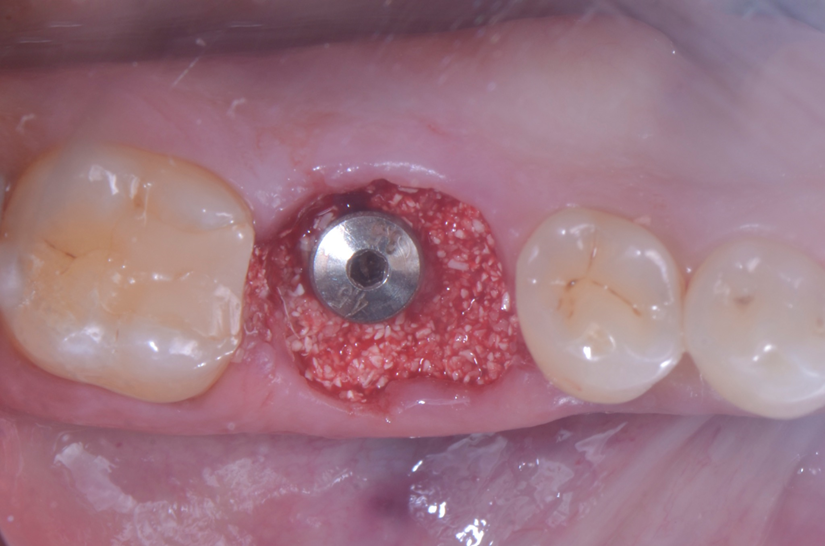

O paciente apresentou fratura vertical mésio-distal no elemento 46. Foi planejada a exodontia minimamente traumática e instalação imediata do implante Maestro Superiore (Implacil Osstem) utilizando uma guia prototipada. Após a exodontia, o implante foi instalado seguindo o protocolo de cirurgia guiada. O GAP vestibular foi preenchido com o Extra Graft. Um cicatrizador personalizado impresso com haletas facilitadoras foi capturado com resina flow e instalado. Após 30 dias, foi realizado escaneamento indireto para obtenção do perfil de emergência, utilizando protocolo digital com sobreposição do cicatrizador escaneado para confecção da coroa definitiva em zircônia policristalina estabilizada por ítria.

A aplicação de biomateriais como o Extra Graft no preenchimento do GAP tem por objetivo preservar o volume alveolar e otimizar a cicatrização3,4. Estudos apontam que o uso de biomateriais associados ao implante imediato resultam em menor reabsorção óssea horizontal e vertical5.